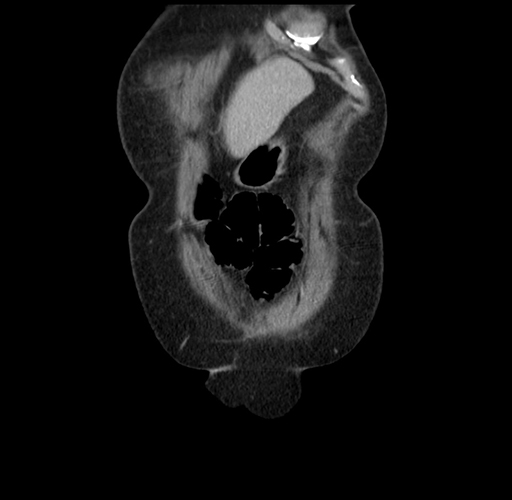

Pre-Chemo: Axial Venous